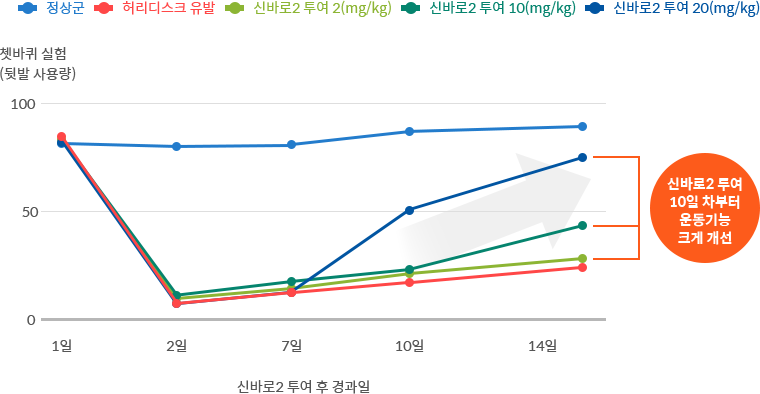

운동 능력 개선 효과

쳇바퀴를 돌게 한 허리디스크 유도 쥐의 움직임 관찰 검사 결과, 신바로 약침 농도가 높을수록 운동기능이 더욱 크게

개선되었습니다.

개선되었습니다.

- 연구기관 : 자생척추관절연구소, 서울대학교 약학대학 연구팀

- 저널명 : Frontiers in Neurology (SCI급 국제학술지) 2023년 3월호

- 논문명 : Effects of the administration of shinbaro 2 in a rat lumbar disc herniation model